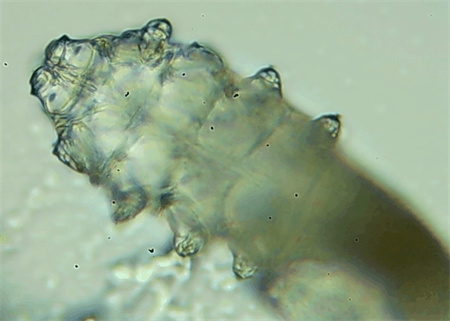

從一只眼睛的上眼瞼和下眼瞼處各拔3根睫毛,放在玻片上。

把玻片放到顯微鏡下觀察,通過(guò)電腦實(shí)時(shí)傳送的畫面,可以查看到這些拔下來(lái)的睫毛上是否有螨蟲。

結(jié)果,有6個(gè)人拔下來(lái)的睫毛上都發(fā)現(xiàn)了螨蟲。

這種螨蟲叫做蠕形螨,他們通常呈乳白色、半透明的細(xì)長(zhǎng)狀,擁有四對(duì)腳。它們跟被子上的塵螨可不是同一種。

這些蠕形螨主要寄生在面部、頭皮、眼睛的睫毛毛囊、睫毛皮脂腺,以及瞼板腺里,以睫毛囊上皮細(xì)胞、腺體內(nèi)脂質(zhì)為食物。因此,即使經(jīng)常換洗床單、衣物,也可能會(huì)有蠕形螨。